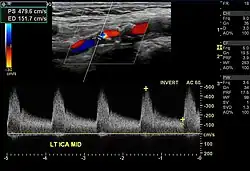

| Stenosegrad in Prozent (NASCET)[8] | Spitzengeschwindigkeit in ACI (cm/s) | Verhältnis Spitzengeschwindigkeit ACI/ACC |

|---|---|---|

| <50 | <125 | <2 |

| 50–69 | >125 | 2–4 |

| 70–89 | >230 | >4 |

| >90 | >400 | >5 |

Nächster Schritt zur Diagnose ist die Untersuchung des Blutflusses in den hirnversorgenden Arterien mithilfe einer farbkodierten Duplex-Ultraschalluntersuchung. Ziel der Untersuchung ist es, den Stenosegrad zu bestimmen, wobei das angiographische Kriterium der Durchmesserreduktion des Lumens als Goldstandard herangezogen wird.[9] Da im Falle einer Verengung des Gefäßes der gleiche Volumenstrom von Blut durch die Verengung fließen muss wie durch das normal weite Gefäß vor und nach der Verengung (→Kontinuitätsgleichung), ist die Geschwindigkeit des Blutes in der Verengung erhöht.[10] Deswegen wird der Stenosegrad im Wesentlichen über die mit dem PW-Doppler gemessene systolische Spitzengeschwindigkeit bestimmt. Zusätzlich wird noch der Quotient aus Spitzengeschwindigkeit in der A. carotis interna und der A. carotis communis herangezogen, um den Einfluss von Bluthochdruck und der Dehnbarkeit der Gefäße zu eliminieren.[9] Darüber hinaus kann mit Ultraschall die Morphologie von Plaques charakterisiert werden, das heißt, die Ablagerungen an den Karotiswänden werden auf ihre Oberflächenbeschaffenheit und Zusammensetzung hin untersucht.[11]